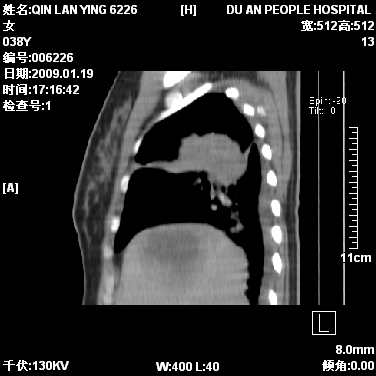

女,38岁,胸疼1个月。wbc:1万4

1)右肺中央型肺癌并右肺上叶阻塞性肺炎、节段性肺不张,纵隔淋巴结转移、右侧胸膜转移、肝脏转移。2)右侧胸腔少量积液。

本病例有几个容易诊断的地方:1、右肺上叶前段支气管闭塞,肺不张。2、淋巴结明显肿大。3、肝脏多个类圆形低密度影呈“牛眼征”改变,高度提示转移。

从影像学角度分析      右肺上叶中央型肺癌,并阻塞性不张、肺炎,纵隔淋巴结、膈顶淋巴结转移。

肝内两个大小不等低密度结节,内可见更低密度影,首先考虑肝内转移瘤,但联想到患者wbc1万4,建议楼主还是做个增强比较明确,除外肝脓肿的可能。